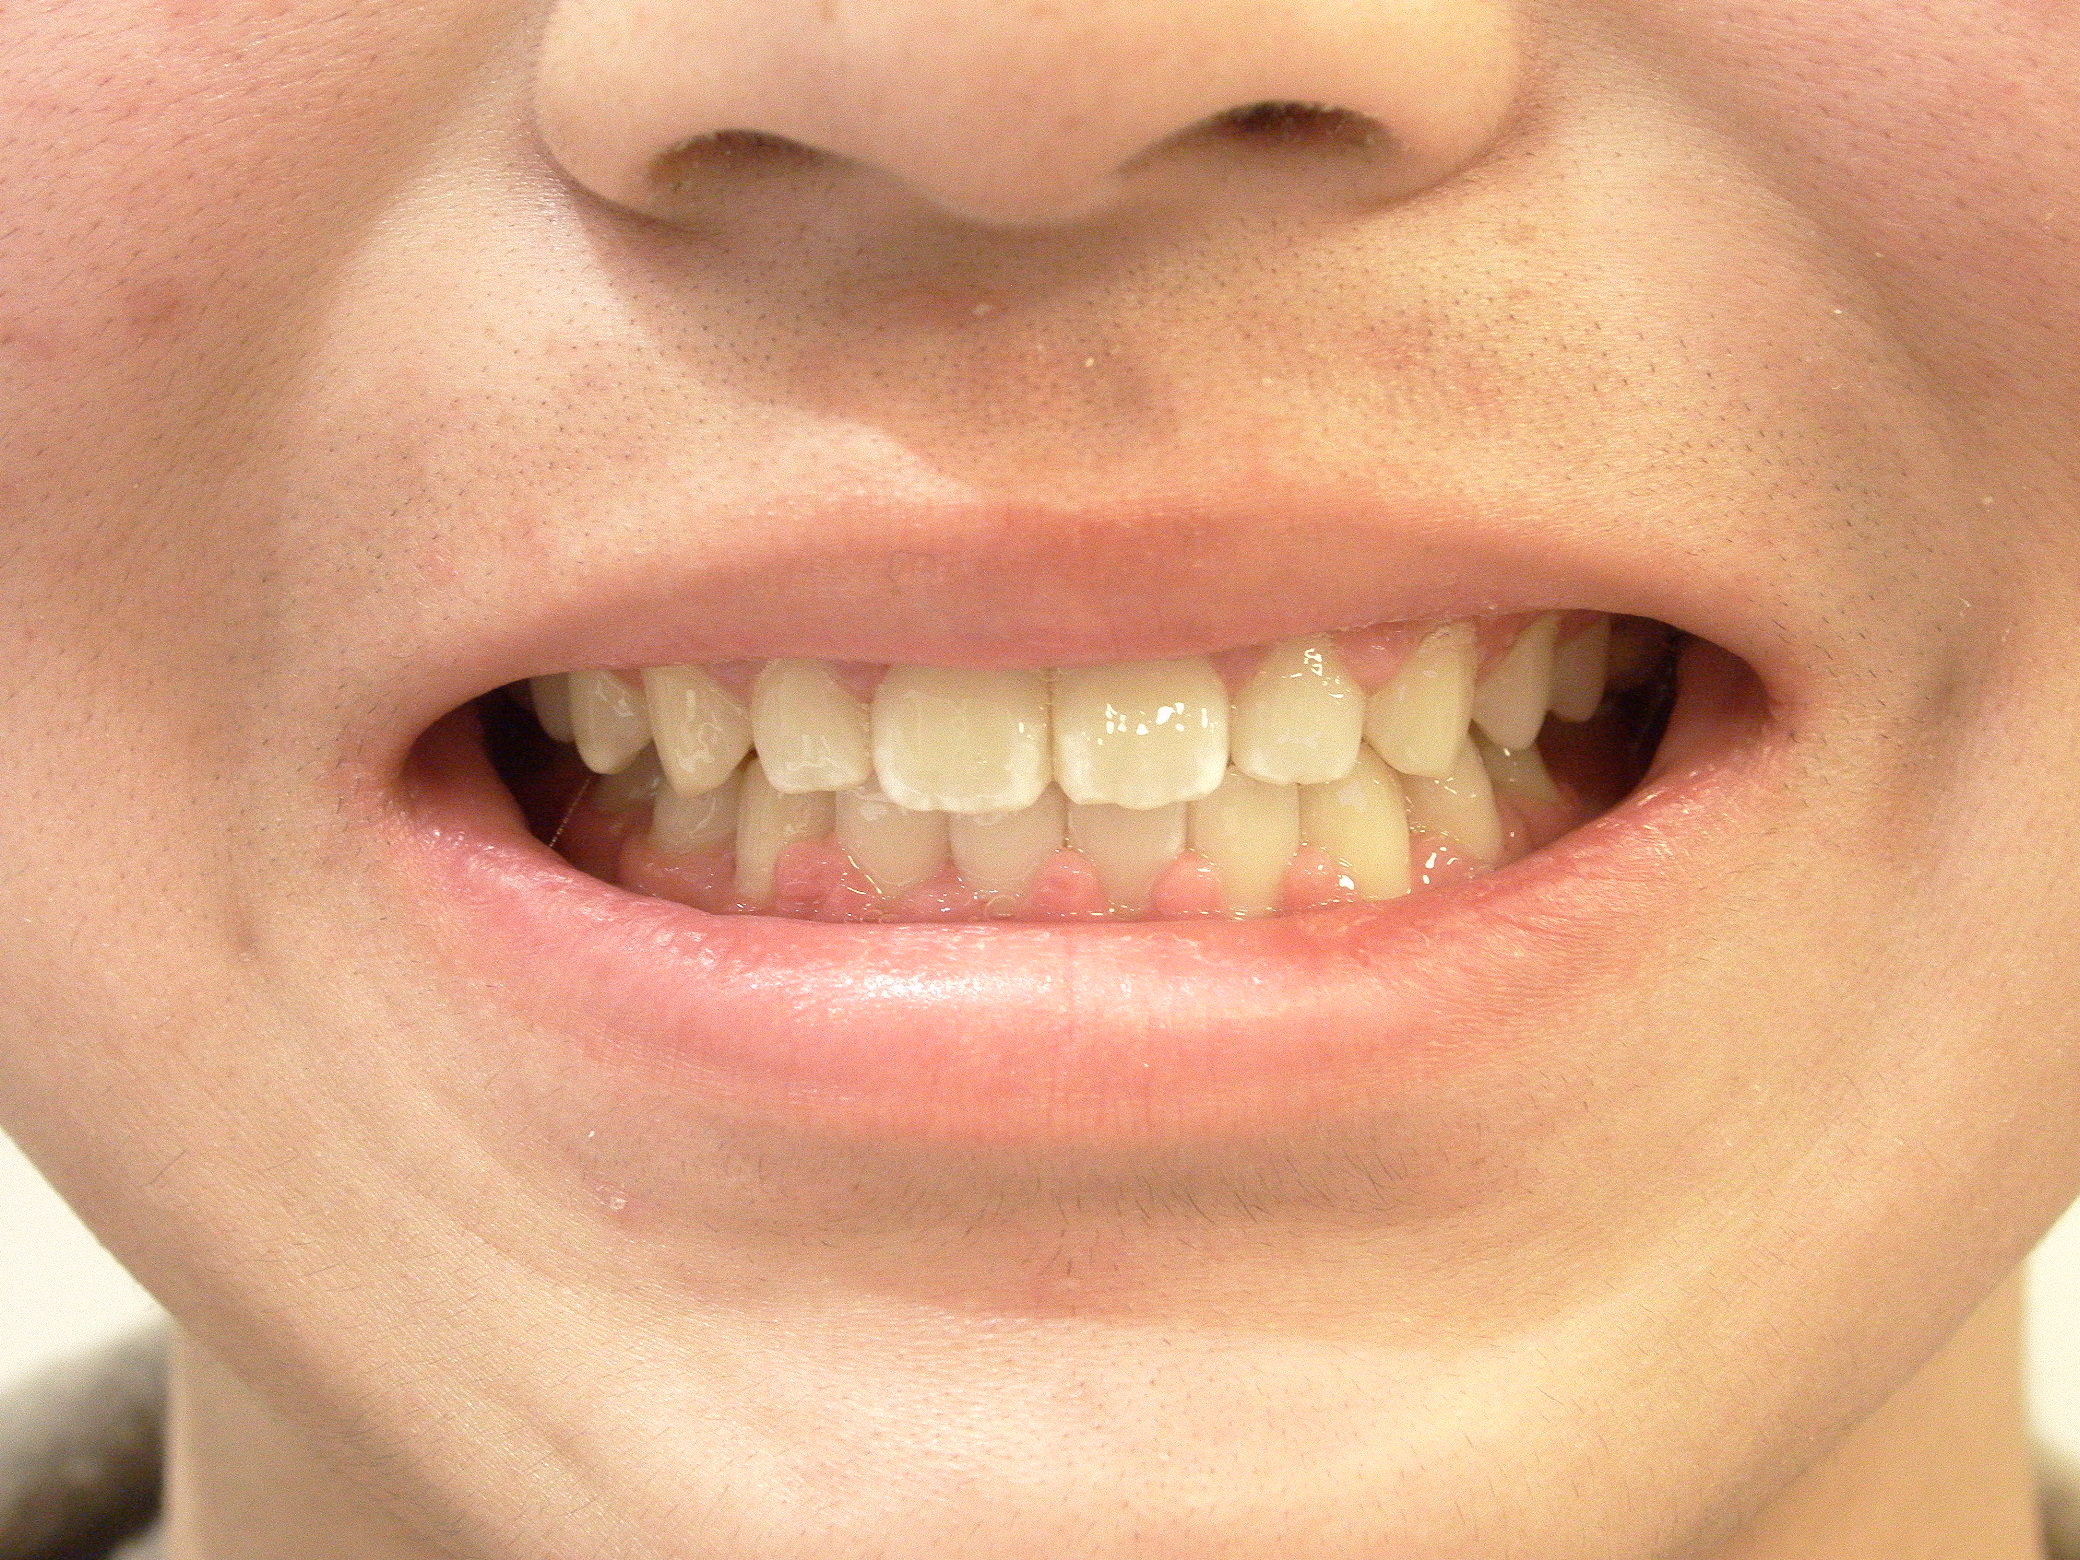

叢生(マウスピース矯正)

7歳 女性

治療例前

カスタムメイド型マウスピース矯正装置(インビザライン)による歯列弓拡大、叢生の改善

カスタムメイド型マウスピース矯正装置(インビザライン)

605,000円(税込)

約1年

マウスピース矯正装置(インビザライン)にて効率よく歯列弓拡大と叢生を改善しています。

ホーレータイプリテーナー(保定装置)を使いながら大人の歯が生えそろうまで経過観察中です。